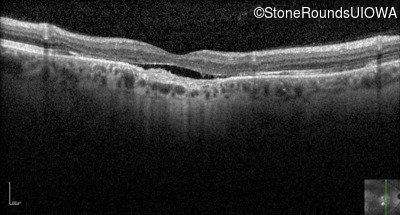

Optical Coherence Tomography - Right - 20/100

Exemplar / OCT Stack

OCT Stack

Optical Coherence Tomography - Left - 20/100